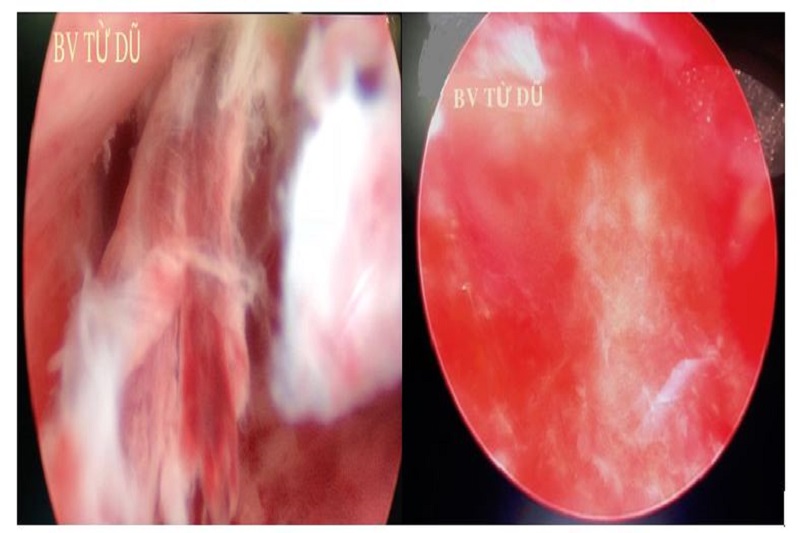

(A) (B)

(A) Hình ảnh polyp lòng tử cung được chẩn đoán bằng nội soi BTC

(B) Hình ảnh BTC sau cắt polyp qua PT nội soi BTC tại BV Từ Dũ